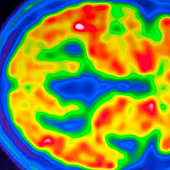

Los autores compararon a esta persona con el caso de la mujer con ADAD. Ambas personas mostraron una patología amiloide generalizada y considerable en el cerebro, que es un sello patológico de la enfermedad de Alzheimer.

Sin embargo, explica a ABC Salud Diego Sepúlveda-Falla, de la Universidad Medical Center Hamburg-Eppendorf, (Alemania), «hubo una agregación limitada de tau (una proteína estabilizadora de microtúbulos en el cerebro) en la corteza entorrinal, una región del cerebro que se ve afectada característicamente en las primeras etapas clínicas de la enfermedad de Alzheimer».